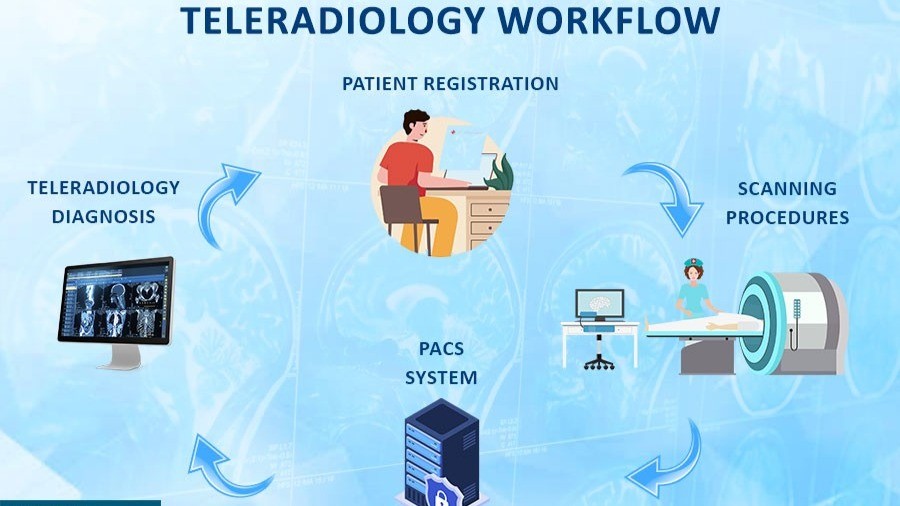

24/7 Teleradiology reporting by experienced radiologists. Trusted by clinics and hospitals for reliable X-Ray, CT Scan Reporting and MRI Reporting result interpretation.